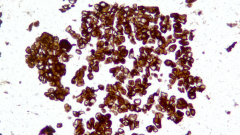

| Description | CLDN18.2是Claudin蛋白質(zhì)家族的一員,位于細(xì)胞膜表面,Claudin18.2(CLDN18.2)表達(dá)具有特異性。其作為Claudins蛋白的一個亞型,在正常組織中僅表達(dá)于分化的胃黏膜上皮細(xì)胞。在胃癌、食管癌和胰腺癌等多種腫瘤中表達(dá),并且不僅限于原發(fā)病灶,在轉(zhuǎn)移灶中也有表達(dá)。目前臨床研究中使用的檢測方法均為免疫組化。 |

| 示例 | ![]() |

| IHC染色結(jié)果 | |